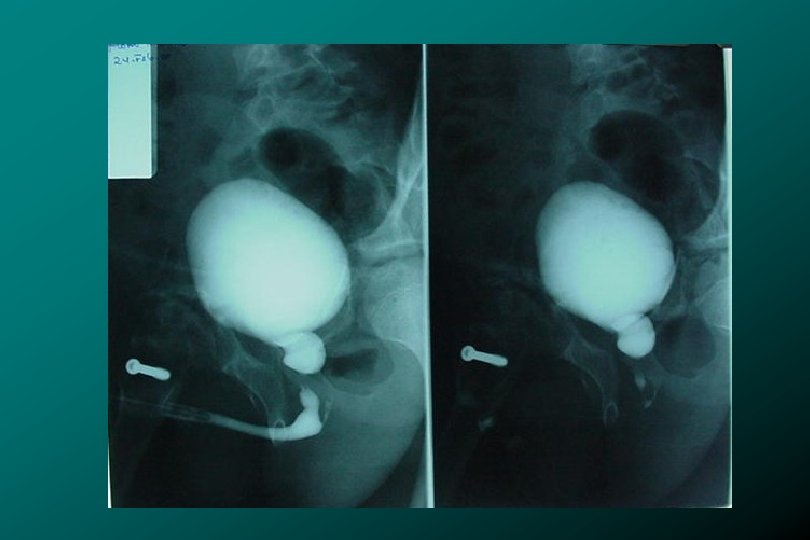

TRAUMA DE URETRA POSTERIOR CLASIFICACIÓN * Tipo III (66%) Ruptura uretra prostatomembranosa Ruptura de

TRAUMA DE URETRA POSTERIOR CLASIFICACIÓN * Tipo III (66%) Ruptura uretra prostatomembranosa Ruptura de Diafragma urogenital. Lesión de uretra bulbar * Zegarra L. : Traumatismos Urológicos. En: Barboza ed. Principios y Terapéutica Quirúrgica. Lima: De Arteta Imp. 1999: 576 -590.